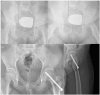

Preoperative (a) and postoperative (b) radiographs of the patient who underwent reduction and fixation with appropriate alignment by the modified Dunn procedure.

Preoperative (a) and postoperative (b) radiographs of the patient who underwent in situ pinning without reduction maneuver.